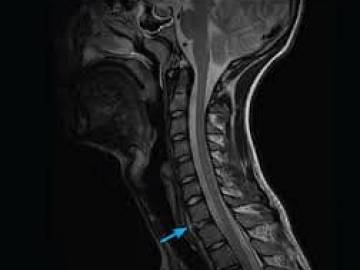

МРТ при межреберной невралгии назначает сделать невролог, когда необходимо определить, какие нервные окончания защемлены и дают боль в груди. Визуализировать все позвоночные структуры грудины можно на МРТ грудного отдела позвоночника. Если боль при межреберной невралгии отдает как в ребро, так и в шею, потребуется сделать комплексную МРТ шеи и грудного отдела позвоночника, чтобы точно разобраться в причинах торакалгии.

МРТ при межреберной невралгии

Точно установить причину межреберной невралгии и дифференцировать ее от кардиологических заболеваний врачам помогает МРТ грудного отдела позвоночника. Магнитно-резонансная томография грудного отдела позвоночника – наиболее надежный и информативный метод обследования мягких и костных тканей позвоночника. Она не требует хирургического вмешательства и, в отличие от рентгена и КТ, выполняется без применения вредного для человека излучения.

Признаки межреберной невралгии на МРТ

На МРТ снимках межреберная невралгия проявит себя следующими признаками

- давление корешков нервных окончаний;

- наличие воспалительных тканей по ходу движения нервов;

- четкий первоисточник зажима.